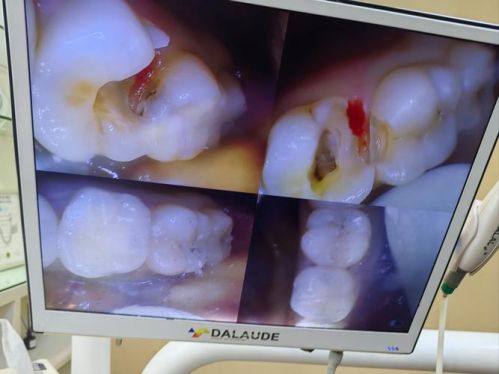

根管治疗

当龋坏比较重度,已经波及到牙髓时,就不得不进行根管治疗了。根管治疗的过程相对复杂一些,医生首先要清除感染的牙髓,然后对根管进行预备和消毒,这一步就像是给牙齿内部进行一次完全的“大扫除”,把细菌和感染物都清除干净。之后再对根管进行严密的充填,防止再次感染。

在根管治疗的过程中,医生还会配合使用氢氧化钙糊剂等根管消毒药物,来进一步保护消毒的成效。根管治疗完成后,为了保护患牙,一般建议进行冠修复,让牙齿能够更好地承受咀嚼压力,修复正常的功能。需要注意的是,根管治疗后可能会出现术后短暂的胀痛,但通常在3 - 5天内就会缓解。